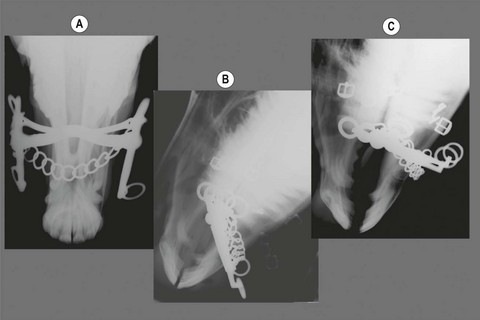

image

Fig. 3.11 Radiographs of bits on full bridles. (A) Ventrodorsal. (B) Lateral without rein pressure. (C) Lateral under rein pressure.